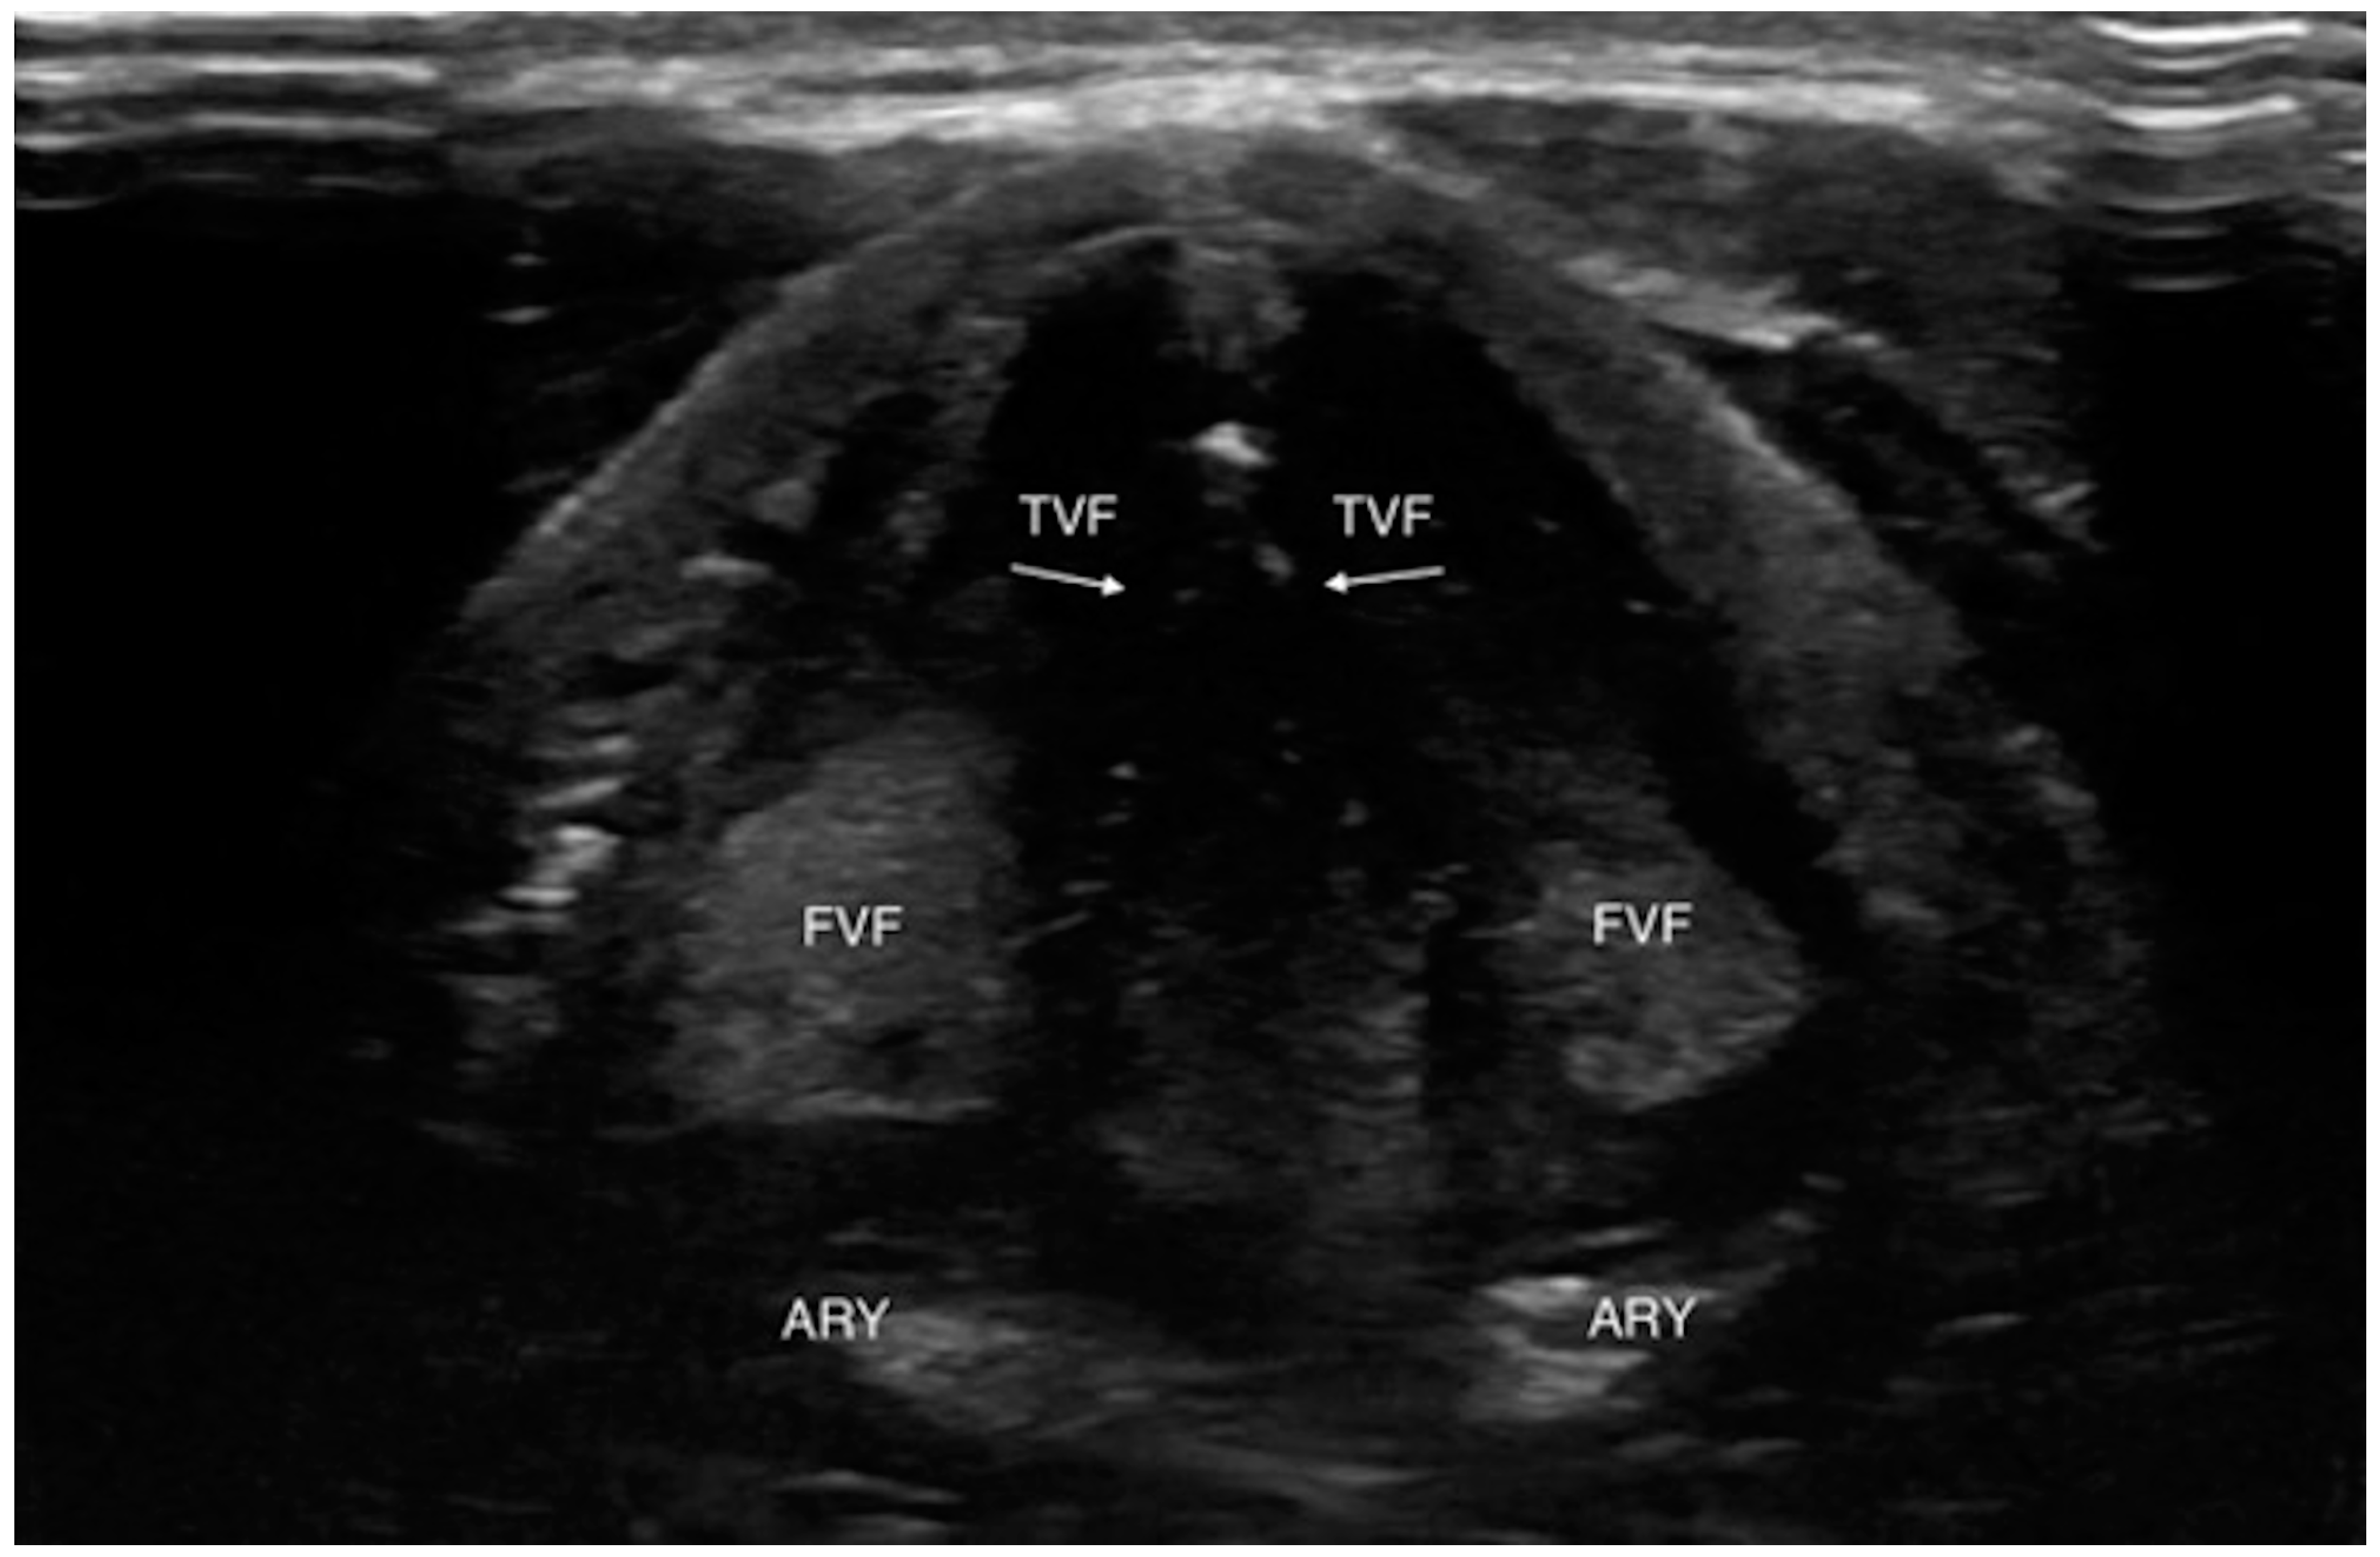

Even if the upper airway US is affected by some limitations due to the presence of artifacts interfering with ultrasound images and interpretation such as subcutaneous emphysema, posterior laryngeal injury, cartilage calcification and foreign bodies, its utilization has been reported in many clinical scenarios [20] (Figure 1 and Figure 2).

Figure 2.

Transverse view of normal vocal folds during relaxation (abduction). ARY, arytenoid; FVF, false vocal fold; TVF, true vocal fold. White arrows indicate hyperechoic medial margins of true vocal folds. Reproduced with permission of Dr. Noel from [20].